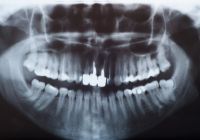

Diagnostic

X-rays are taken on check-up visits to diagnose any decay or other hygiene problems. A panoramic film or full mouth x-ray is taken every 3-5 years to observe tooth or jaw growth. |